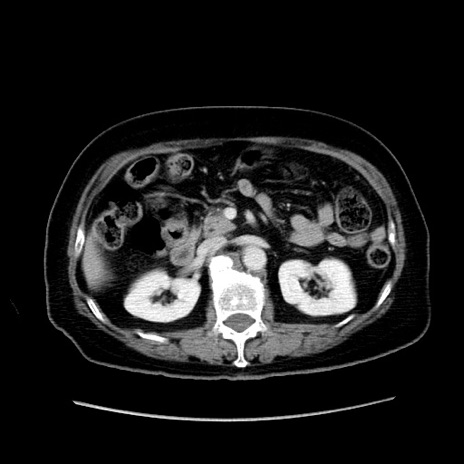

症例19(横断像)

【症例】80歳代女性

【主訴】下腹部痛

【現病歴】約8時間前より下腹部痛の出現あり、救急外来受診。

【既往歴】両側付属器切除

【身体所見】意識清明、下腹部正中に手術痕あり、その部位に一致して圧痛と反跳痛あり。腸蠕動音は亢進。

【データ】WBC 9300、CRP 0.15